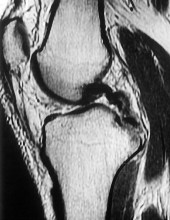

Question 4:

A 22-year-old female soccer player undergoes primary anterior cruciate ligament (ACL) reconstruction using a bone-patellar tendon-bone autograft. Postoperatively, she experiences loss of terminal extension and anterior knee pain. An MRI indicates graft impingement against the intercondylar roof. Which of the following technical errors during tunnel preparation is the most common cause of this specific impingement pattern?